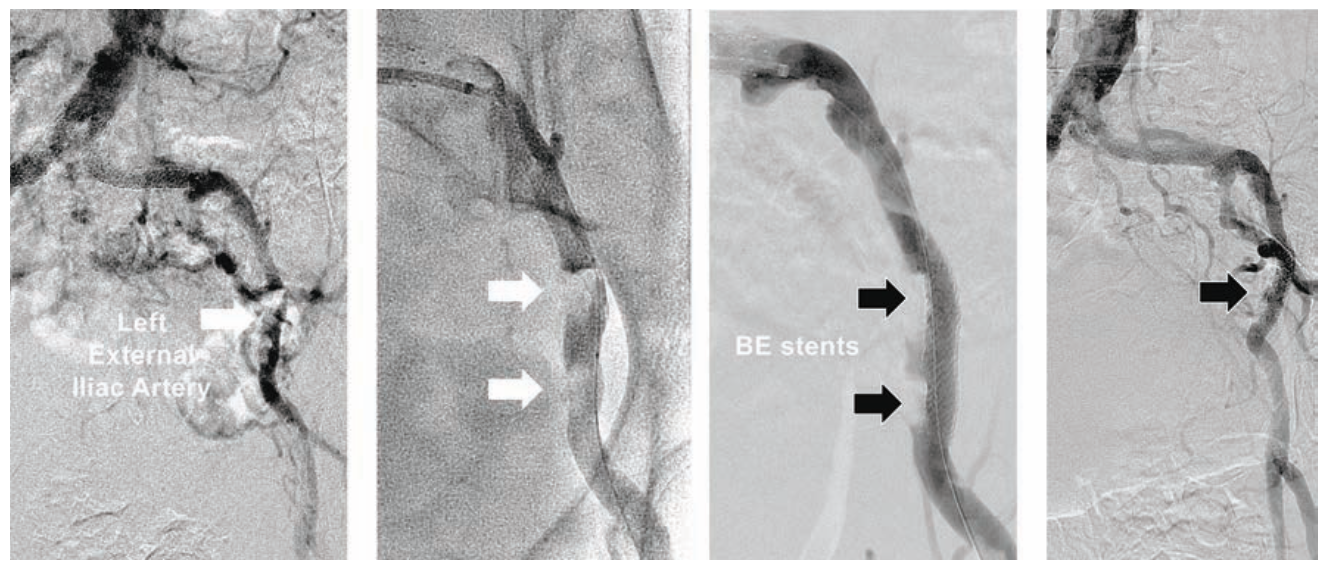

Case #4

A 72-year-old Asian female (5 feet, 152 cm in height) with debilitating left greater than right buttock and thigh claudication was found to have resting ABIs falling with exercise from 0.80 down to 0.65 in the right leg, and 0.68 down to 0.40 in the left leg. Diagnostic angiography using 5 Fr right TRA demonstrated severe bilateral common and external iliac artery disease, and internal iliac artery occlusions (Figure 4), with no significant infrainguinal vascular disease. A 300 cm Wholey guidewire was used to direct a 110 cm 5 Fr Flexor Shuttle sheath into the distal abdominal aorta, with advancement of a 300 cm coronary guidewire across each iliac artery. Pre-dilatation was performed in both iliacs using a Viatrac 14 Plus RX 7 mm x 15 mm PTA balloon. Subsequently, two overlapping EverFlex Entrust 8 mm x 80 mm SE stents were deployed in each iliac artery to treat the diffuse disease. Post deployment was performed with the Viatrac 14 Plus RX balloon. The patient was discharged 3 hours later following use of a TR Band.

Tips and Tricks for 5 Fr Bilateral Iliac Artery Stenting

5 Fr TRA for iliac artery stenting can be accomplished in most women with peripheral Herculink Elite RX BE stents up to 7 mm in diameter and 18 mm in length, and EverFlex Entrust SE stents up to 8 mm in diameter and 150 mm in length. Primary therapy for bilateral aortoiliac ostial disease in women with small radial arteries can be performed using bilateral radial access and .014-inch guidewires. Advancement of two 5 Fr Sublime 120 cm guide sheaths into the terminal abdominal aorta will facilitate pre-dilatation with “kissing balloons” using two Viatrac 14 plus RX PTA balloons, followed by two Herculink Elite RX BE “kissing stents” up to 7 mm in diameter. Endovascular therapy for short iliac artery CTOs has been accomplished using 5 Fr TRA. However, most operators may prefer 6 Fr or 7 Fr femoral artery access for treating women with iliac CTOs, so that the rare complication of iliac artery perforation can be immediately treated using stent-graft implantation with a Viabahn endoprosthesis (Gore). Lower profile .018-inch Viabahn delivery catheters currently require 6 Fr for 6 mm devices, and 7 Fr for 7 mm and 8 mm devices, and are available only in 120 cm catheter lengths.